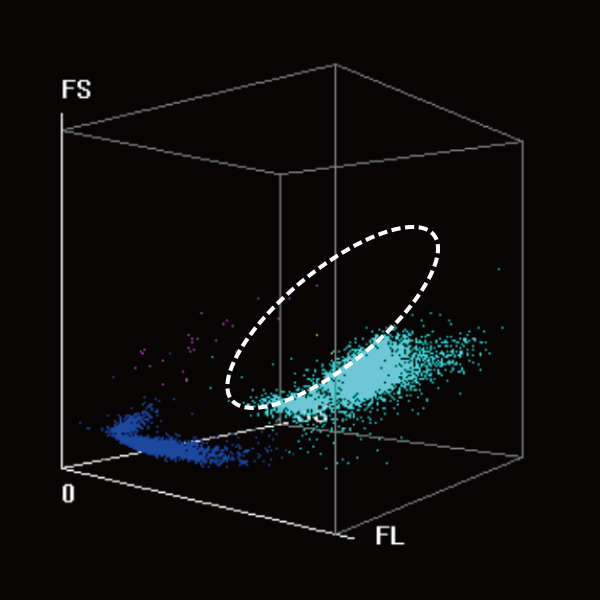

High Sensitivity and Specificity of Blast Flagging Capability for Preliminary Screening

The coordinated analysis technology of WNB and DIFF scattergarms give sensitive alerts for РђюBlasts" with high specificity to reduce unnecessary labor-intensive manual microscopy.

DIFF 3D scattergram

Coordinated analysis

WNB 3D scattergram

Abn. Lymph/blast?

Abn. Promyelocyte/blast?